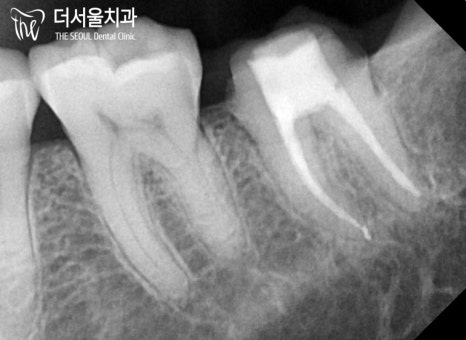

계획했던대로 감염된 치수 조직을 제거한 뒤,

충전재를 사용하여 뿌리 끝(apex)까지

빈 공간이 없도록 채워넣었습니다.

뿌리 끝까지 확실하게

채워진 것을 확인할 수 있는데요.

몇차례의 확인을 거쳐

확실하게 밀폐된 것을 확인한 뒤

신경치료 과정을 마쳤습니다.